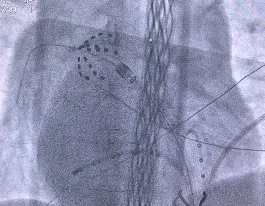

术中造影显示患者下腔静脉极度迂曲,无法经下腔静脉途径送入导管。团队果断改为左腋静脉入路,使用AccuSafe穿刺导丝联合Navigo 8.5Fr可调弯鞘进行房间隔穿刺,并采用本中心首创的Y阀造影剂显影方法确认进入左房。术中借助可调弯鞘灵活适配至上腔静脉入路角度,实现与房间隔稳定贴靠;依托穿刺导丝的滑脱保护及穿刺兼导引的双重安全特性,避免了误穿心包、主动脉及鞘管前冲损伤,在X线引导下精准、安全完成穿间隔操作,充分体现了团队的娴熟技术与应变能力。随后送入Farapulse PFA导管,对双侧肺静脉及上腔静脉进行消融隔离,共放电37次,验证完全阻断,手术获得成功(见图4)。

脊柱畸形患者CT图像(左)、术中下腔静脉影像(中)、电生理团队实施经左腋静脉入路PFA手术(右)

左1左2为房间隔穿刺过程;右1肺右上肺静脉花瓣状消融;右2:左上肺静脉网篮状消融